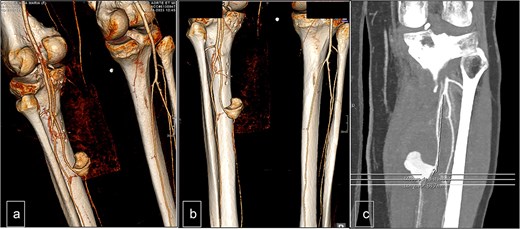

Surgical intervention was performed, consisting of open resection of the pseudoaneurysm at the proximal portion of the PTA, followed by patchoplasty with an autologous vein graft from the homolateral limb. The posterior tibial vein was ligated during the procedure (Fig. 3).

(a) Preoperative view. (b) Preoperative view. PTA after resection of the pseudoaneurysm and before the autologous patchoplasty.